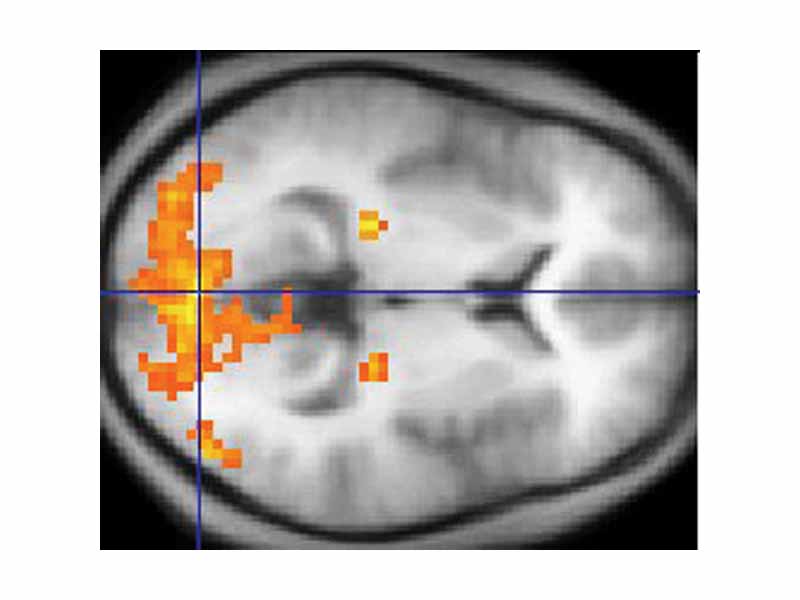

A scan of the brain using fMRI